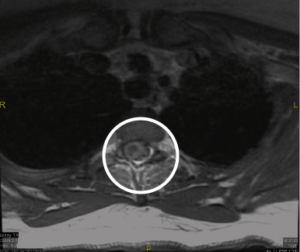

Figure 3: Thoracic MRI expressing cord edema and expansion, presumably reflecting venous congestion/hypertension. The cord appears to be scalloped due to dilated perivascular vessels.